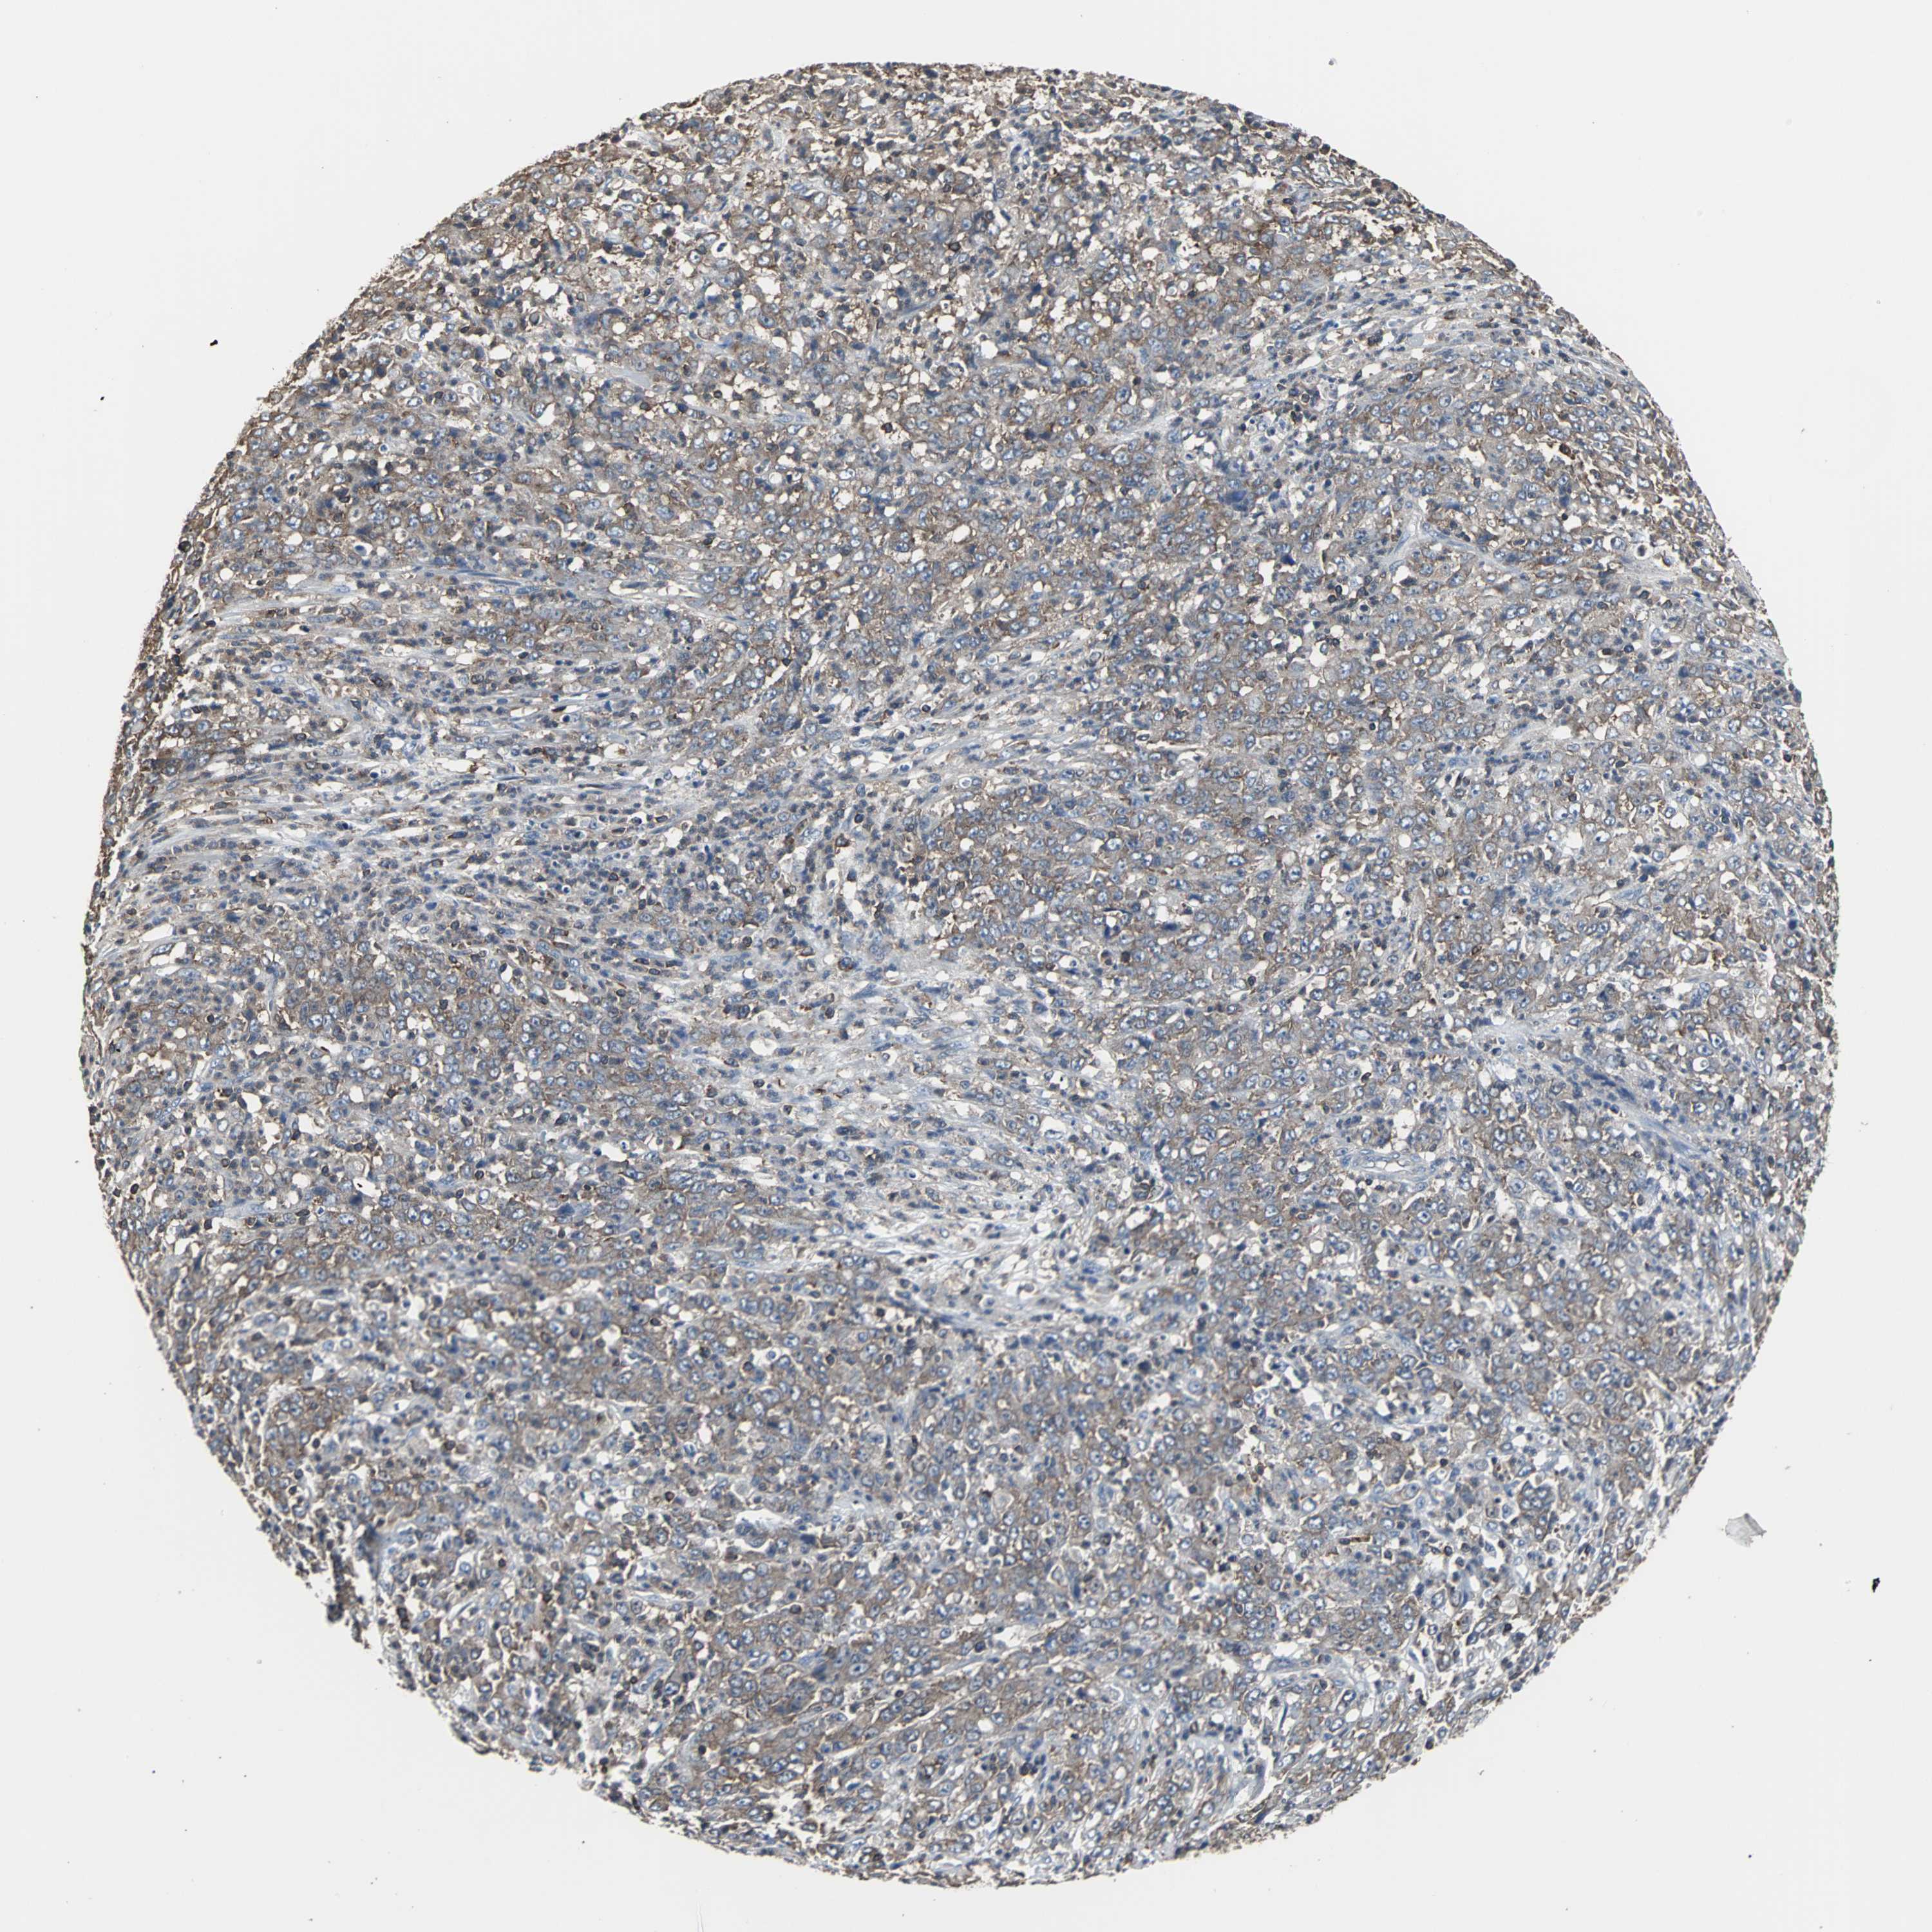

STOMACH CANCER - Protein expressioni

A mouse-over function shows sample information and annotation data. Click on an image to view it in a full screen mode. Samples can be filtered based on level of antibody staining by selecting one or several of the following categories: high, medium, low and not detected. The assay and annotation is described here.

Note that samples used for immunohistochemistry by the Human Protein Atlas do not correspond to samples in the TCGA dataset.

Antibody stainingi

Antibody staining in the annotated cell types in the current human tissue is reported as not detected, low, medium, or high, based on conventional immunohistochemistry profiling in selected tissues. This score is based on the combination of the staining intensity and fraction of stained cells.

Each image is clickable and will lead to virtual microscopy that enables deeper exploration of all samples and also displays staining intensity scores, fraction scores and subcellular localization as well as patient and tissue information for each sample.

Antibody HPA006979

Staining

High

Medium

Low

Not detected

Intensity

Strong

Moderate

Weak

Negative

Quantity

>75%

75%-25%

<25%

None

Location

Nuclear

Cytoplasmic/membranous

Cytoplasmic/membranous,nuclear

Adenocarcinoma, NOS

Adenocarcinoma, High grade